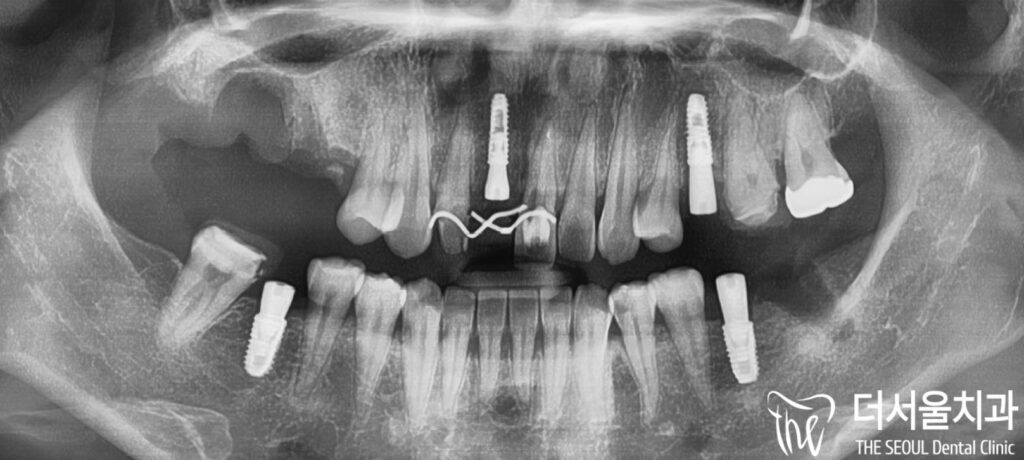

먼저 정확한 진단을 위해

엑스레이를 촬영해 보았습니다.

임플란트 수술 과정에서 중요하게

여겨져야 되는 것은

이머전시 프로파일(emergency profile)을

잘 살려주는 것입니다.

『 emergency profile 이란? 』

인공 치아 뿌리에서부터

보철로 이어지는 라인을

일컫는데, 이 라인을 자연치와

유사한 상태로 각지지 않게

만들어 줘야 됩니다.

만약, 이곳이 각지거나

턱지게 된다면 어떻게 될까요?

정답은 음식이 잘 끼고

빠지기 쉽지 않기 때문에

다음과 같은 부작용이

생길 수 있습니다.

1. 주위 잇몸 염증

2. 염증으로 인한 퇴축

그러므로 알맞은 보철 수복이

이루어질 수 있게 노력해야 됩니다.